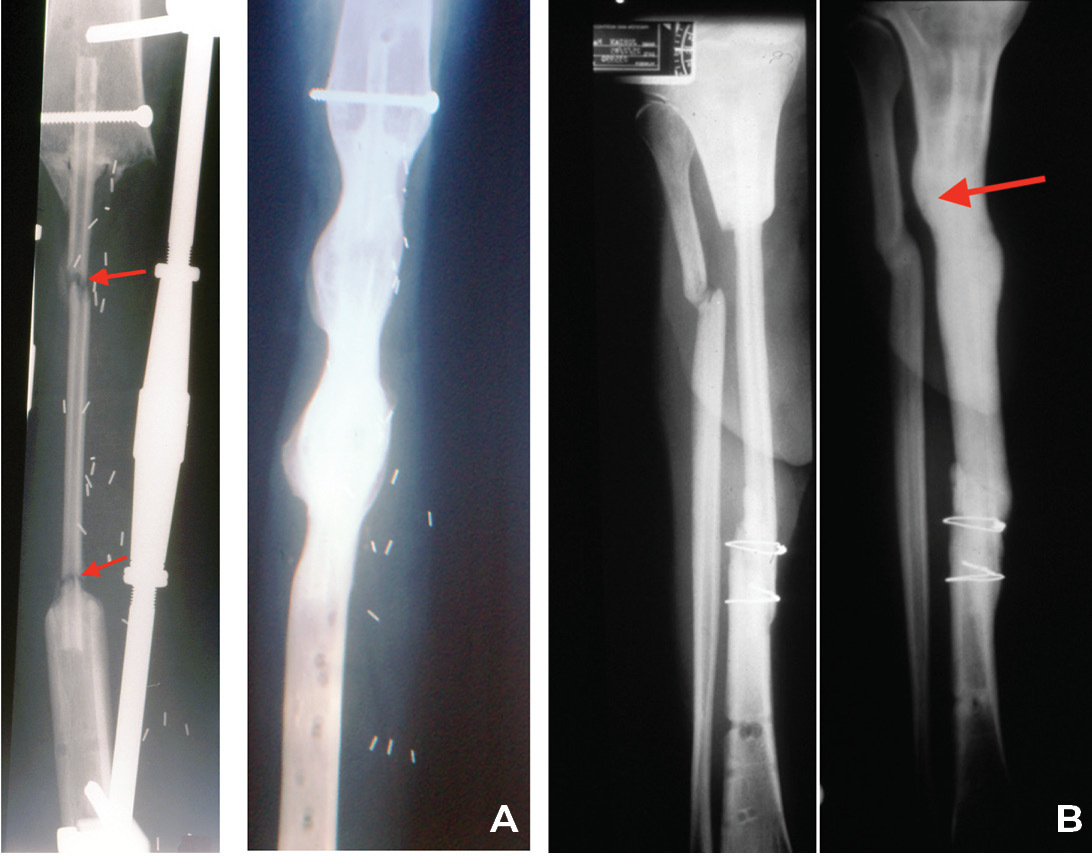

Another form of fixation is an intramedullary nail or rod used in two of our nine cases of resection of a pseudarthrosis of the tibia in a child shown in Cases 12 and 13 (Figures 32 and 33). In these two cases, the distal tibial fragment could not be fixed to the fibula with a screw. Instead a Rush nail was passed from below through the heel, calcaneum, talus and distal tibia and into the medullary cavity of the transplanted fibula. The result was exactly the same as the other seven cases. Even in plaster you can’t keep a child still! By six weeks all, including the two with nails, showed union and early bone hypertrophy (Figures 32 and 33).